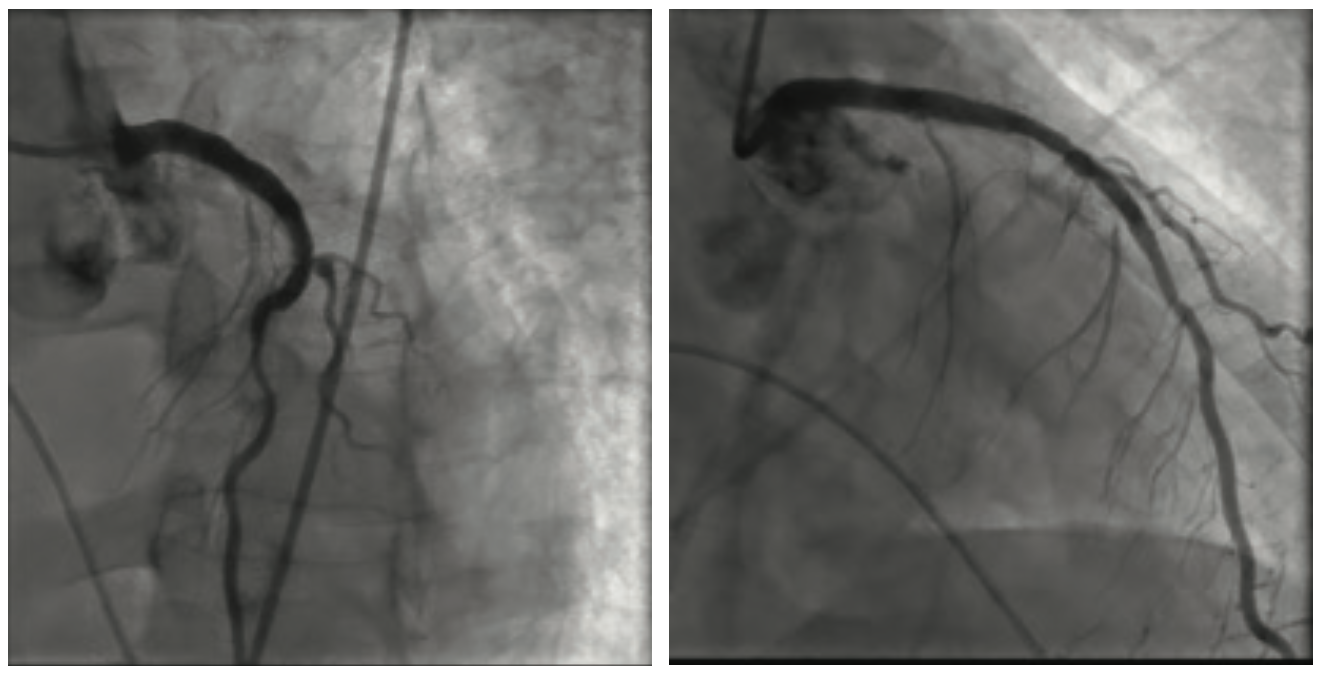

He clinically improved and on the second hospital day, underwent diagnostic cardiac catheterization. He did not have palpable radial pulses bilaterally; therefore, a femoral approach was used. His right external iliac artery and right common femoral artery were occluded. His distal aorta was heavily calcified with a high-grade eccentric stenosis. He also had a proximal 70%-80% left common iliac artery stenosis. Diagnostic coronary angiographic findings demonstrated a heavily calcified ostial 99% lesion in the right coronary artery (RCA) with significant calcium accumulation throughout the mid RCA. The left main coronary artery appeared heavily calcified, with a wedge-shaped filling defect suggesting a high-grade eccentric stenosis. The proximal left anterior descending (LAD) artery was very tortuous with a heavily calcified lesion at the first diagonal that extended into the ostium of the diagonal vessel. The circumflex artery was totally occluded. The patient’s ejection fraction based on ventriculography was 35% to 40%, with the posterior lateral wall being akinetic. He was extubated following the cardiac catheterization. Cardiothoracic surgery was consulted to provide an opinion regarding surgical revascularization. Due to his multiple comorbidities, he was felt to be high risk and not a surgical candidate. A plan for percutaneous revascularization was discussed with the patient. The nature and purpose of the procedure along with expected outcomes, together with the reasonably known risks were explained. He acknowledged that such disclosure of information had been made and that all questions asked about the procedure had been answered. He demonstrated understanding and legal capacity to consent and therefore, the written consent was obtained by his signature. The intervention was performed on hospital day 5. The patient was discharged home on hospital day 7.

The RCA was initially treated with orbital atherectomy. The 1.25 mm x 145 cm Diamondback 360˚ orbital atherectomy system (CSI) was advanced over the wire. Multiple passes at low speed were performed to reduce the ostial RCA lesion. Treatment was performed from proximal to distal, with the tip of the catheter crown just within the ostium prior to spinning. After multiple passes, luminal gain was observed angiographically in the ostial portion of the vessel. The crown was then traversed on low speed through the mid RCA just proximal to the distal portion of the vessel. Balloon angioplasty was performed prior to deploying two drug-eluting stents to cover the orbital atherectomy treatment zone from the distal RCA retrograde to cover the RCA ostium. No slow flow or dissections were noted angiographically and the patient remained hemodynamically stable throughout the RCA intervention. A Xience Skypoint 2.75 mm x 33 mm stent (Abbott Vascular) was advanced into the distal RCA and deployed at 12 atmospheres (atm). This was followed by a 3.0 mm x 33 mm Xience Skypoint stent, deployed in the mid RCA, and finally, a 3.5 mm x 28 mm Xience Skypoint stent was deployed proximally. The stents were post dilated with a 3.0 mm x 20 mm, 3.5 mm x 20 mm, and 4.0 mm x 20 mm NC Trex RX balloon (Abbott Vascular) at 20 atm. Completion angiography was performed. We chose to proceed to treating the left coronary tree.

The left main artery was cannulated with a 6 Fr XBLAD 3.5 guiding catheter (Cordis). The Whisper wire was used to cross the stenosis. IVUS was performed using an .014 Eagle Eye Platinum ultrasound catheter (Philips Volcano). In the same fashion as the RCA, the Whisper wire was exchanged for the ViperWire. The LM was subsequently treated with orbital atherectomy. Multiple passes were performed in opposition to the 70% nodular, calcified lesion that was fully identified on IVUS imaging. Once luminal gain was identified angiographically in the LM, the atherectomy crown was traversed distally into the calcified lesion in the proximal LAD. After two passes in the proximal LAD, the crown was traversed into the mid LAD lesion at the level of the first diagonal branch. Orbital atherectomy was again performed, reducing the calcium burden in both the LAD and the ostium of the diagonal branch. Balloon angioplasty was performed from mid LAD retrograde to the LM using a 3.0 mm x 20 mm NC Trek balloon. Following the balloon angioplasty, drug-eluting stents (3.0 mm x 15 mm Xience Skypoint, 3.5 mm x 38 mm Xience Skypoint, and a 5.0 mm x 30 mm Resolute Onyx drug-eluting stent [Medtronic], placed distal to proximal) were deployed from the mid LAD proximally to the LM, covering the orbital atherectomy-treated zone. The patient remained hemodynamically stable throughout the procedure. A completion angiogram was obtained. No slow flow or dissections were noted.